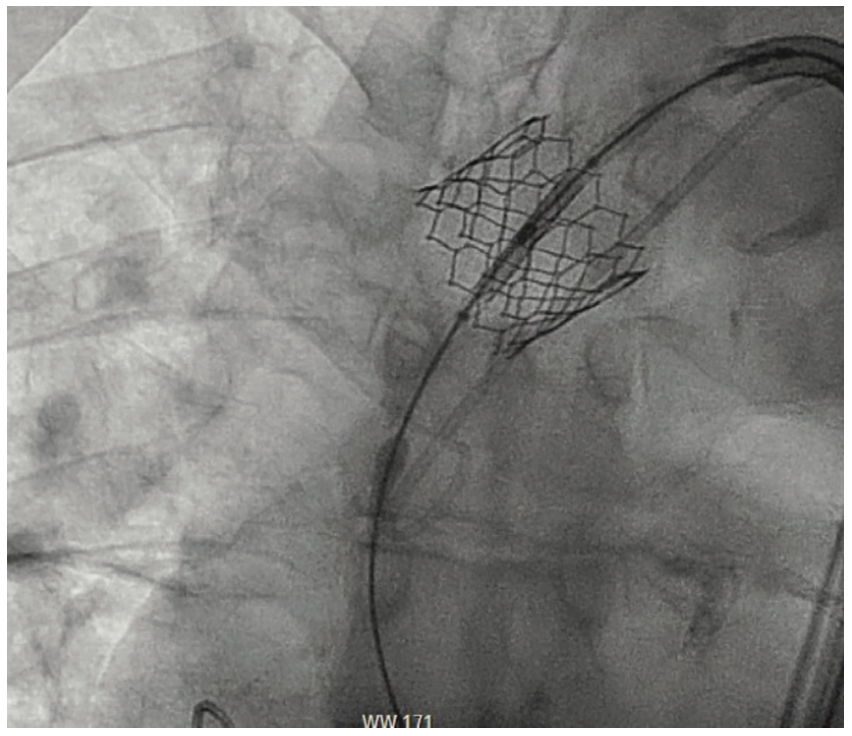

During the TAVR procedure, a Sapien 3 26 mm valve was loaded over a Safari wire (Boston Scientific) and advanced into the aortic annulus under fluoroscopy, with good planar angle positioning confirmed using contrast injection. After valve placement, rapid ventricular pacing was performed and the valve was deployed. However, immediately following deployment, the valve embolized into the ascending aorta. The valve was carefully pulled distally and secured just proximal to the origin of the right brachiocephalic artery. It was dilated with an extra 4 mL volume with two inflations performed. To confirm the patency of the right subclavian artery and the right brachiocephalic artery, access was subsequently obtained in the right radial artery, and no difference in the arterial pressure was noted as the catheter was advanced from the right radial artery into the aortic root. A second Sapien 3 26 mm valve was then loaded over the Safari wire and was similarly advanced into the aortic annulus under fluoroscopy, with good coplanar angle positioning confirmation via contrast injection. After rapid ventricular pacing, the second valve was deployed without issue. A post procedure aortogram confirmed good valve positioning, the absence of significant paravalvular leak, and patency of the left coronary artery. A limited echocardiogram also confirmed good valve positioning, the absence of paravalvular leak, and the absence of pericardial effusion. The patient tolerated the procedure well and left the cardiac catheterization laboratory in a stable condition. After chest x-ray confirmed stable positioning of the embolized valve in the ascending aorta, the patient was discharged on postoperative day one with a scheduled follow-up visit in three weeks.